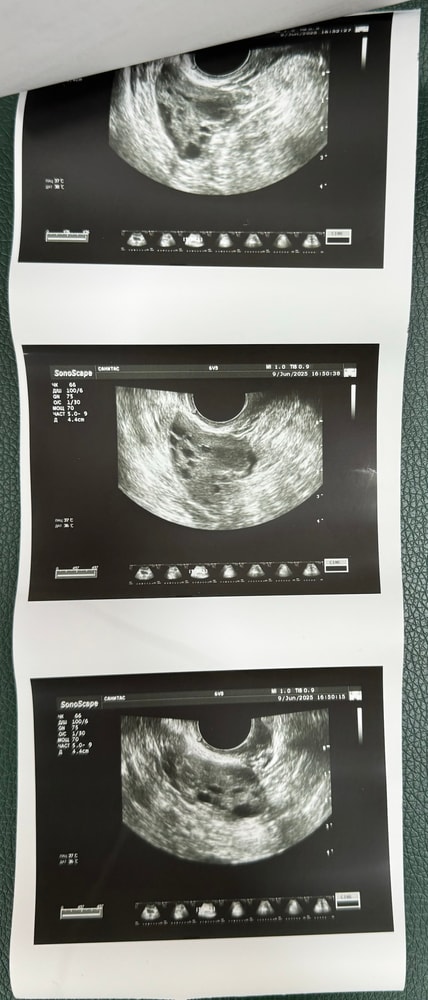

у меня она вот выглядит, нижняя